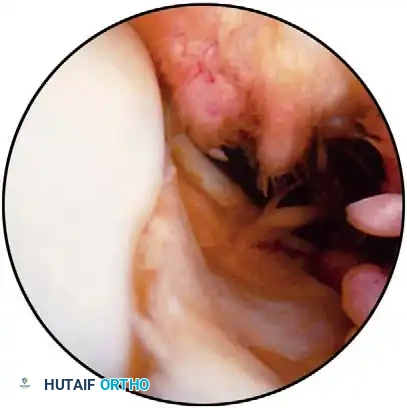

Vertical Longitudinal (Bucket-Handle) Tears This common tear usually occurs in young patients as a result of signifi cant trauma. It frequently is associated with an anterior cruciate ligament injury, and the medial side is more commonly involved than the lateral side (approximately 3:1). Long tears that extend at least two thirds of the circumference of the meniscus produce an unstable fragment that locks into the joint by displacing in toward the notch (Fig. 48-17). The patient typically has episodes of locking in which the knee can be neither fully extended nor fl exed. The fragment may displace and reduce with an audible and palpable clunk. There is associated pain and effusion. Occasionally, the bucket-handle fragment permanently displaces into the intercondylar notch. In these situations, the patient is gradually able to resume most activities, but knows that something is wrong with the knee. The fragment may become distorted and fi xed in place. Other bucket-handle tears divide in their central portion, creating two separate fl aps, one based anteriorly and the other posteriorly. A patient with a suspected bucket-handle tear who may be a candidate for meniscal repair should have this possibility discussed before arthroscopy. The most common criteria for meniscal repair include (1) a vertical longitudinal tear more than 1 cm in length located within the vascular zone, (2) a tear that is unstable and displaceable into the joint (Fig. 48-18A), (3) an informed and cooperative patient who is active and younger than 40 years old, (4) a knee that either is stable or would be stabilized with a ligamentous reconstruction simultaneously, and (5) a bucket-handle portion and remaining meniscal rim that are in good condition. Chronically deformed or degenerative menisci are not good candidates for repair. Rubman, Noyes, and Barber-Westin evaluated 198 surgical repairs, a major portion of which were in the avascular region. At 18month follow-up, 80% were asymptomatic, and 20% had repeat surgery. Of the 91 repairs that were reevaluated

Fig. 48-17 A, Bucket-handle tear of medial meniscus that has fl ipped into intercondylar notch; in this position, meniscus may cause intermittent symptoms. B, Locked buckethandle tear of medial meniscus. arthroscopically, 25% were healed, 38% were partially healed, and 36% had failed. Most investigators report that only 10% to 15% of meniscal tears are reparable, and that most such repairs are done in association with an anterior cruciate ligament reconstruction. Bucket-handle tears that are not reparable can be treated with partial meniscectomy. Early reports suggest that preserving a meniscal rim eventually would lead to better long-term results, particularly in stable joints with a normal weight bearing axis. Schimmer et al. reported 92% goodto-excellent results at 4-year follow-up and 78% at 12-year follow-up after arthroscopic partial meniscectomy in 119 patients. Articular cartilage damage was the main determinant of long-term function. Sixty-two percent of patients had good-to-excellent results if chondral damage was present; 95% had good-to-excellent results if normal articular cartilage was present at the time of arthroscopic surgery. Partially displaceable tears usually are shorter and confi ned to the posterior half of the meniscus. Often, these

Fig. 48-18 A, Unstable 2-cm peripheral tear of meniscus. Meniscus is being repaired with stacked vertical mattress suture. B, Incomplete undersurface tear of medial meniscus; this can be treated with abrasion to stimulate local healing followed by placement of one or two sutures. C, Complete 2-cm tear in avascular zone of meniscus; this type of tear generally is treated with excision, but if repair is attempted, use of fi brin clot and other local stimuli should be considered. shorter tears are located peripherally and can be repaired. Tears that are less than 5 to 7 mm in length and stable to probing during which the tear does not displace more than 1 mm can have the edges and perimeniscal synovium freshened with a meniscal rasp. Talley and Grana noted a 21% failure rate at short-term follow-up of 19 patients with stable partial-thickness medial meniscal tears that were treated with perimeniscal rasping. For lateral tears, 4% failed. These authors recommended repair of partial-thickness medial tears. We also believe that an aggressive treatment approach should be used for medial meniscal tears. When the decision has been made to perform a partial meniscectomy, the choice must be made as to whether to use a two-portal or three-portal technique. If the meniscal fragment has displaced into the notch, it should be reduced using either a probe or a blunt trocar. If the meniscal fragment is large or chronic, the medial compartment may have to be opened with fl exion and a valgus stress to permit reduction of the fragment. The technique for resecting a displaced bucket-handle tear and the technique for resecting a nondisplaced, short, vertical, longitudinal tear are essentially the same. In each situation, a probe should be introduced, and the tear should be examined with the probe to determine the anterior and posterior extents. The probe also can be used to plan the subsequent cuts. This examination usually is most easily conducted with the arthroscope in the anterior portal contralateral to the tear and the probe in the ipsilateral portal.

Fig. 48-19 Two-portal technique for bucket-handle tears of lateral meniscus. A, Displaced bucket-handle tear of lateral meniscus probed. B, After reduction of displaced bucket-handle tear, posterior attachment is partially released with scissors. C, Anterior attachment is released with scissors. D, Tenuous remaining posterior attachment is avulsed with grasper and extracted. probe passes into the inferior tear, but not through to the superior surface of the meniscus. Vigorous attempts to hook the probe into an unseen inferior tear should be avoided for danger of extending the tear. If such a tear exists, gentle probing can make the inner border of the meniscus buckle and evert (see Fig. 48-18B). Stable peripheral one-third tears in relatively healthy menisci should be treated by abrasion of the tear site and meniscal synovial tissue to stimulate healing, preserving meniscal function. If stability is in question, suturing may be indicated for most medial meniscal tears (see “Arthroscopic Surgery of the Meniscus” earlier).